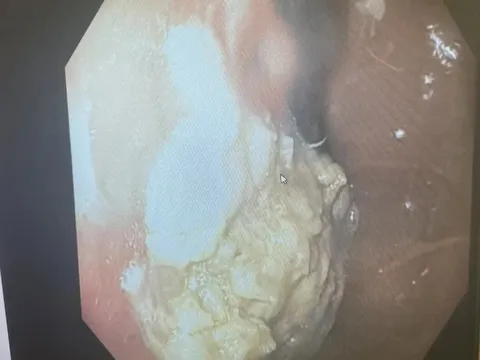

Điều gì xảy ra khi đứa trẻ 5 tuổi nuốt 40 chiếc kẹo cao su?

TPO - Một cậu bé 5 tuổi ở Ohio, Mỹ đã trải qua một thủ thuật để loại bỏ một cục kẹo cao su bị mắc kẹt trong dạ dày, theo một nghiên cứu trường hợp được công bố trên JEM Reports.